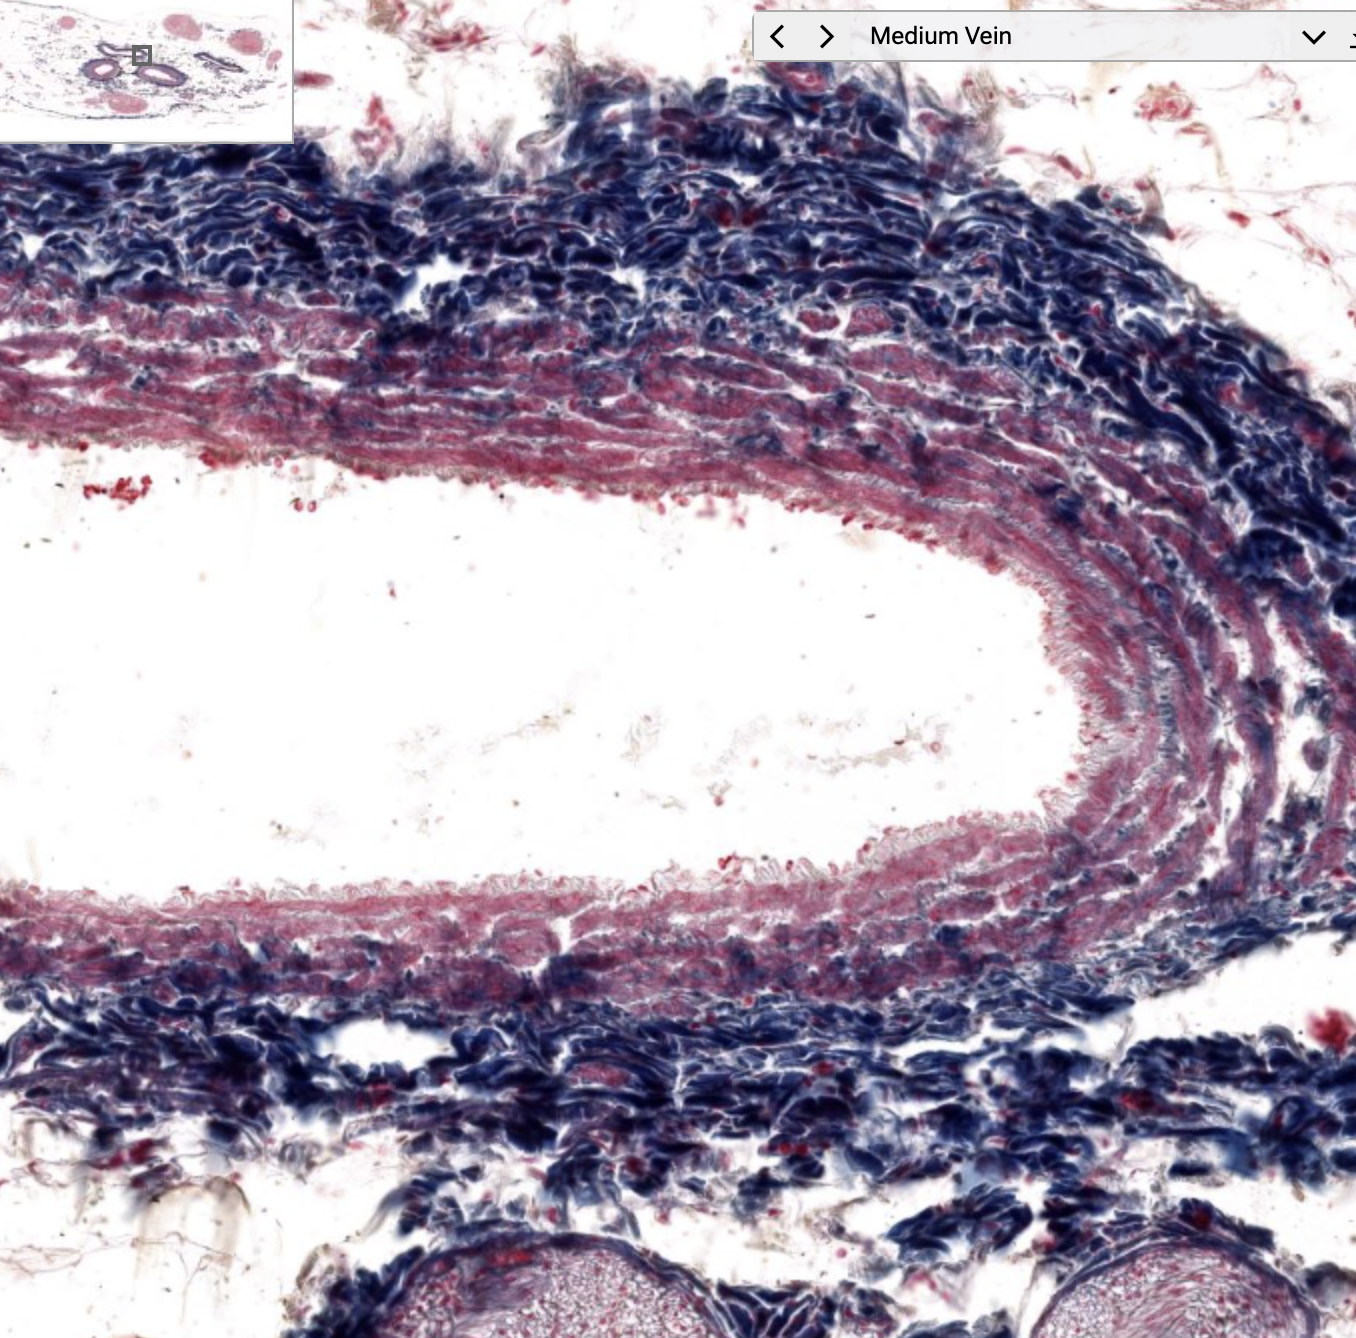

muscular artery and medium vein

vein

medium vein

Medium veins have?

Thin layer of smooth muscle.

tunica adventitia (may have vaso vasorum)

Many have flap valves to prevent back flow

Medium veins

Thin tunica intima and media but thick tunica adventitia